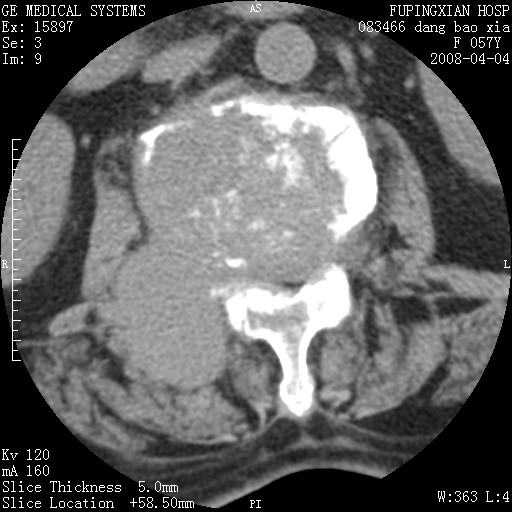

标题: CT12677:女性,57岁,疼痛数月。 [打印本页]

标题: CT12677:女性,57岁,疼痛数月。

椎体及附件骨质破坏同时伴软组织肿块,首先考虑恶性肿瘤。

椎体及附件骨质破坏,伴软组织肿块,首先考虑恶性骨肿瘤,建议提供正侧位片。

椎体及附件骨质破坏,伴软组织肿块,首先考虑恶性,不排除转移瘤.

椎体及附件溶骨性破坏,周围巨大软组织肿块,首先考虑转移瘤。

椎体及附件骨质破坏同时伴软组织肿块,首先考虑恶性肿瘤,不排除转移瘤。